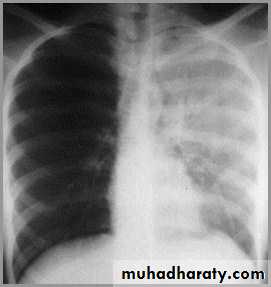

Differentiating the Causes of an Opacified Hemithorax

Pneumonia of an entire lung

pneumonia

The hemithorax is opaque and there isno shift of the heart or tracheaThere may be an air bronchogram sign present